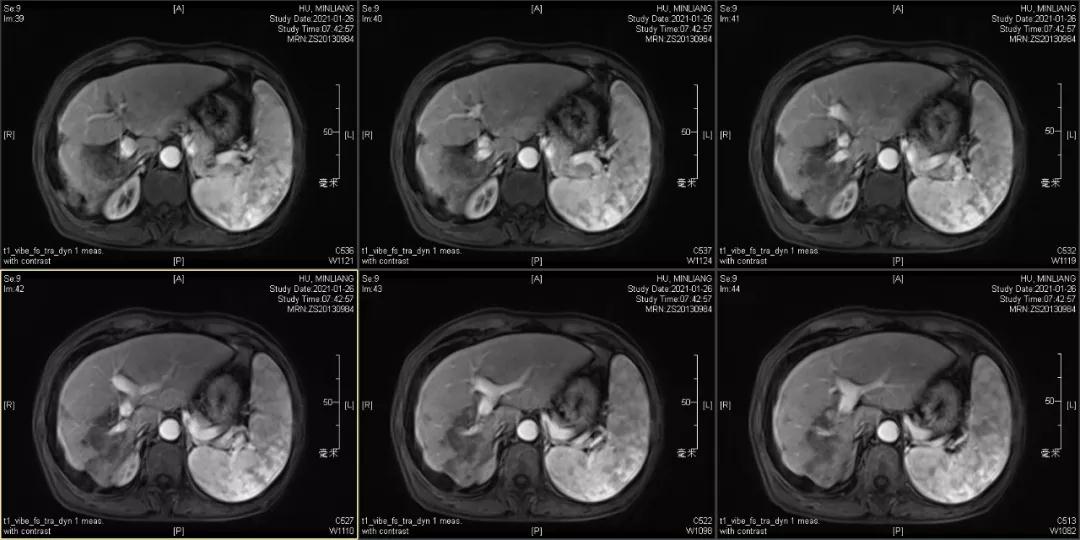

用药6个月后:肝脏病灶明显缩小,子灶消失,仅有少量动脉期强化;肺转移单个持续缩小稳定,PET CT活性弱;HBV DNA 转阴;可考虑转化切除。

2021-2-1 手术切除:右半肝切除术+胆囊切除

术后病理:病理学CR

术后1月复查:磁共振肝内未见肿瘤复发,肺部单个肿瘤稳定。

术后末次随访2021年12月6日,肝内未见明显病灶,肺部病灶稳定1.3cm。